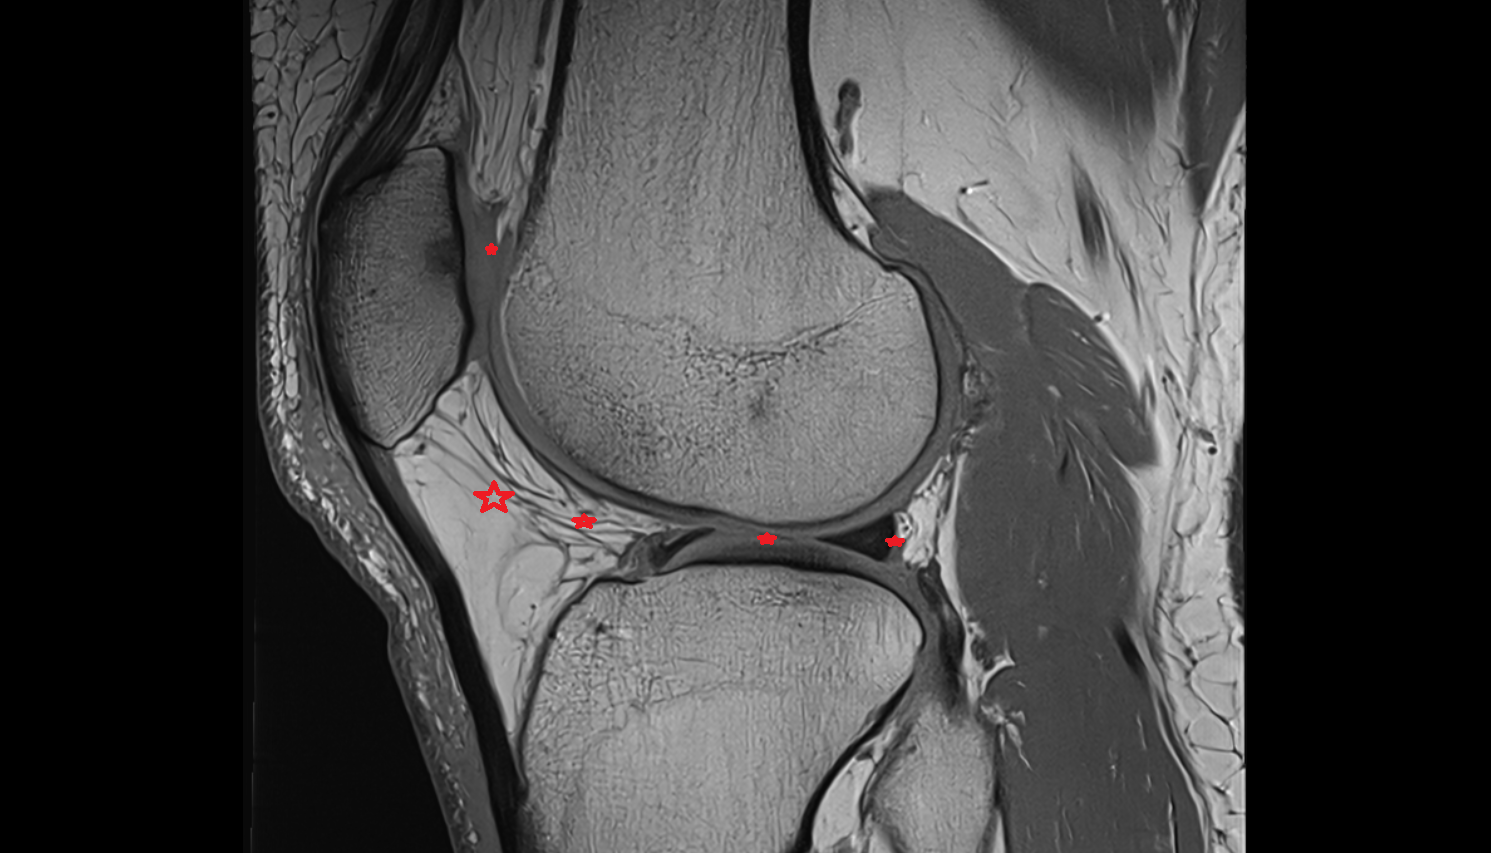

- Anterior cruciate ligament

- Posterior cruciate ligament

- Medial meniscus

- Lateral meniscus

- Posterior horn of medial meniscus

- Posterior horn of lateral meniscus